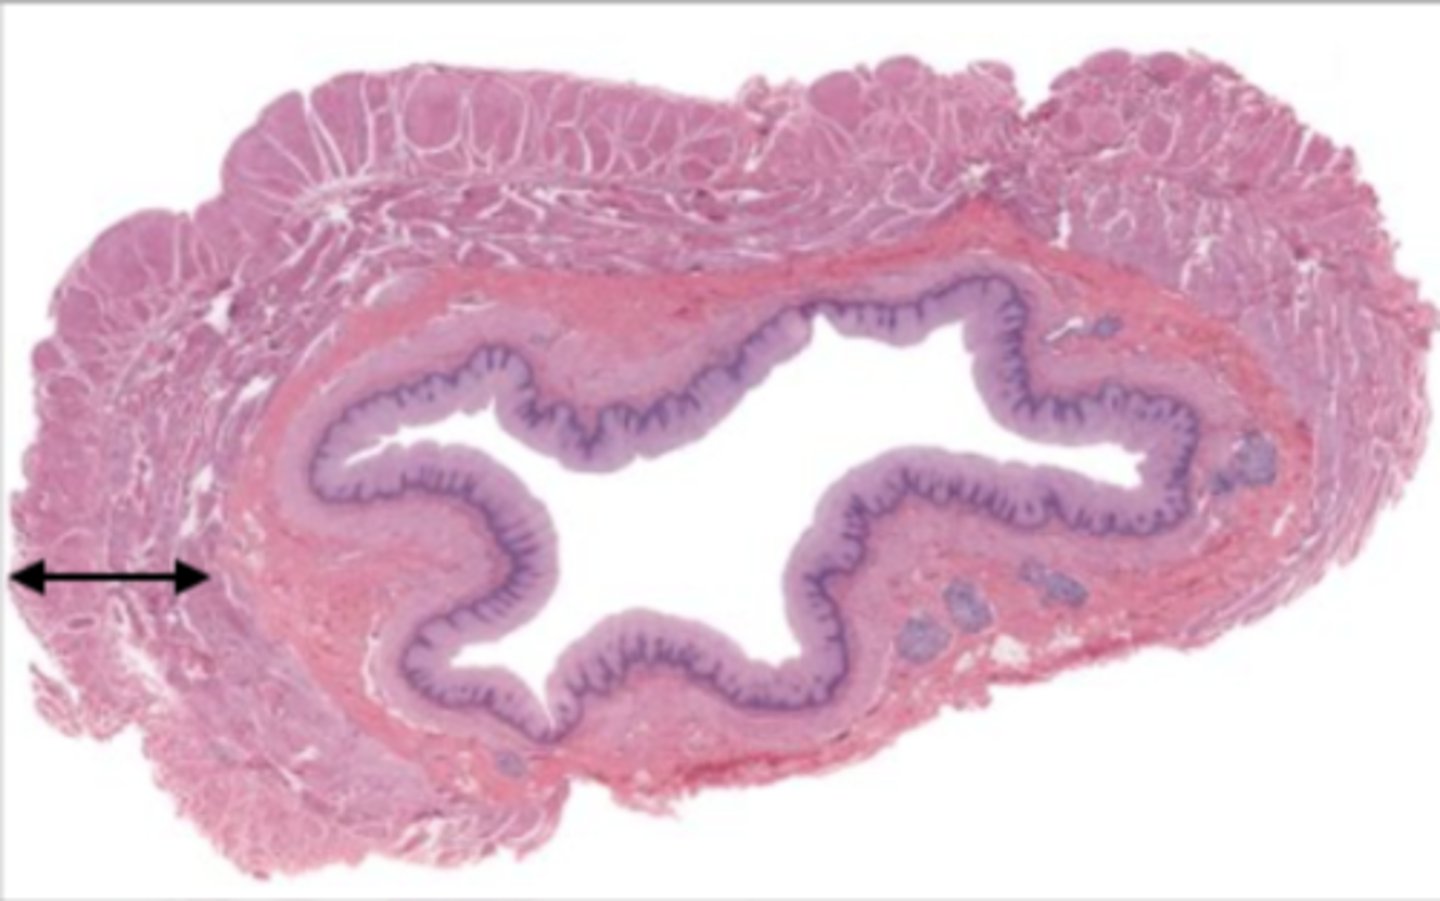

gallbladder (histology)

gallbladder

this tissue's wall structures/layers are different than the rest of the organs

simple columnar epithelium

what kind of epithelium lines the mucosa of the gallbladder

lumen (gallbladder)

mucosa (gallbladder)

mucosal epithelium (gallbladder)

lamina propria (gallbladder)

muscularis mucosa and submucosa

gallbladder tissue does not have _______ and ______

muscularis externa (gallbladder)

serosa/adventitia (gallbladder)